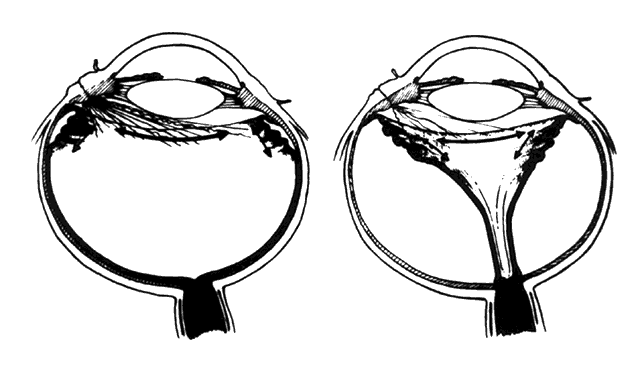

Cleary and Ryan15 reported experimental evidence that blood and, to a lesser extent, lens material in the presence of a large scleral wound caused fibrocellular proliferation and membranes, the contraction of which produced tractional retinal detachments (Fig. 4). The clinical consequences of fibrocellular proliferation and membrane contraction are well established and include traction retinal detachments, retinal breaks, rhegmatogenous retinal detachments, proliferative vitreoretinopathy, cyclitic membranes, ciliary body detachments, hypotony, and phthisis bulbi.

Fig. 4. Fibrocellular proliferation and membrane formation cause tractional retinal detachment. (Cleary PE, Ryan SJ: Method of production and natural history of experimental posterior penetrating eye injury in the rhesus monkey. Am J Ophthalmol 88:219, 1979. Published with permission from The American Journal of Ophthalmology. Copyright by The Ophthalmic Publishing Company.)

Retinal detachments caused by contracting membranes are characteristic of penetrating injuries.20 Shrinking transvitreal membranes initially cause traction detachments of the retina opposite the site of scleral perforation (Fig. 6). In approximately 40% of cases, continued traction causes a dialysis at the vitreous base and consequent rhegmatogenous retinal detachment (Fig. 7).20 Retinal incarceration in a scleral perforation produces a less common but equally characteristic traction retinal detachment (Fig. 8). Retinal folds radiate from the site of incarceration. Associated vitreous prolapse and entrapment cause traction on the adjacent vitreous base with consequent detachment of the underlying peripheral retina and pars plana epithelium. A retinal fold is created at the posterior border of the vitreous base, which becomes increasingly prominent because of the contracture of membranes interposed between the vitreous base and the incarceration site. Progressive traction by this membrane may cause breaks in the folded retina and consequent rhegmatogenous detachment (Fig. 9).

Fig. 6. Transvitreal traction causes tractional retinal detachment (A) opposite perforation site (B). (Michels RG, Wilkinson CP, Rice TA: Vitreous Surgery. Retinal Detachment, p 210. St. Louis, CV Mosby, 1990)

Fig. 7. Retinal dialysis caused by traction of shrinking membrane. Location of scleral laceration (A). Vitreous membrane (B). Dialysis at vitreous base border (C). (Cox MS, Freeman HM: Retinal detachment due to ocular penetration. I. Clinical characteristics and surgical results. Arch Ophthalmol 96:1355, 1978. Copyright 1978, American Medical Association.)

Fig. 8. Retinal incarceration in scleral perforation. Fibrous proliferation from wound (A). Vitreous membrane (B). Retinal folds (C). Detached pars plana epithelium (D). Fold at posterior vitreous base border (E). (Cox MS, Freeman HM: Retinal detachment due to ocular penetration. I. Clinical characteristics and surgical results. Arch Ophthalmol 96:1355, 1978. Copyright 1978, American Medical Association.)

Fig. 9. Retinal incarceration in scleral perforation. Dialyses in sharp fold at posterior vitreous base border (A). Dialysis at anterior vitreous base border (B). (Cox MS, Freeman HM: Retinal detachment due to ocular penetration. I. Clinical characteristics and surgical results. Arch Ophthalmol 96:1355, 1978. Copyright 1978, American Medical Association.)